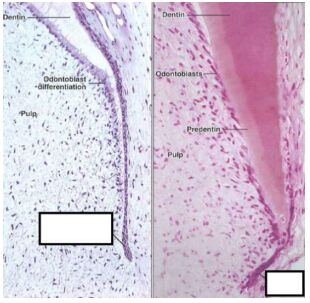

8. 下圖黑線白底框框中之構造稱? (A)牙釉島(B)牙釉結(C)牙突島(D)側牙版

29.右圖方框中構造稱為?

(A)Herwig’s epithelial root form(B)Hertwig‘s epithelial root canal(C)Hertwig‘s epithelial root shell(D)Hertwig‘s epithelial root sheath